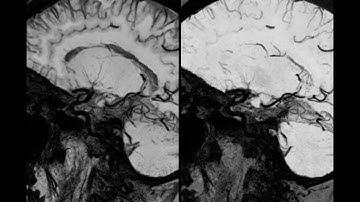

High resolution 3D HyperCube T2 with AIR Recon DL and HyperSense